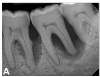

(7.) Progressive improvement in bone quality, quantity, and morphology during each time period, especially in the furcation area of tooth No. 18, which shows a noticeable narrowing of the width of the bony defects, slight apical resorption of the distal root of tooth No. 18, and the encasing of residual cementum on the distal root of No. 19 by new bone formation. Periapical radiographs were taken of teeth Nos. 17, 18, and 19 on June 25, 2016, January 28, 2017, August 23, 2019, and September 4, 2020, respectively, the final of which was taken after almost 5 years post-initial scaling and root planing and alternating supportive periodontal maintenance.

Figure 7

(8.) Progressive improvement in bone quality, quantity, and morphology during each time period, especially in the furcation area of tooth No. 18, which shows a noticeable narrowing of the width of the bony defects, slight apical resorption of the distal root of tooth No. 18, and the encasing of residual cementum on the distal root of No. 19 by new bone formation. Periapical radiographs were taken of teeth Nos. 17, 18, and 19 on June 25, 2016, January 28, 2017, August 23, 2019, and September 4, 2020, respectively, the final of which was taken after almost 5 years post-initial scaling and root planing and alternating supportive periodontal maintenance.

Figure 8

The patient's periodontal disease improved with initial nonsurgical periodontal therapy that involved scaling and root planing. This initial treatment was followed by only SPT every 3 months. Despite treatment, residual deep periodontal probing depths remained, so a decision was made to maximize improvements with nonsurgical therapy and to reassess as needed to determine whether surgical intervention was appropriate. After almost 5 years of SPT and good patient compliance with plaque control and supportive care, the periodontium was stable. Because of the resulting bone formation and improvements in clinical attachment levels (Figure 7 through Figure 13), it was determined that periodontal surgical intervention was not necessary.

In the case report presented, treatment with nonsurgical therapy for 5 years effectively halted destruction and led to bone regeneration and improved clinical attachment levels. Although the primary etiology of periodontal disease is well documented, secondary etiologic and contributing factors are numerous.16 After initial therapy in the current case, there was radiographic evidence of a hypercementosis-like lesion on the distal root of tooth No. 19 (Figure 7 through Figure 10). Hypercementosis is a nidus for plaque accumulation leading to disease progression; however, the presence of this lesion did not explain the disease severity observed for tooth No. 18. Chronic periodontitis is the most widespread form of periodontal disease, and nonsurgical periodontal therapy is the most common type of therapy.17 Scaling and root planning is the gold standard for periodontal treatment. When performed meticulously, they result in improvement of clinical parameters through changes related to tissue shrinkage, long junctional epithelium, new attachment, and in rare circumstances, regeneration.18 The use of nonsurgical periodontal therapy for treatment of periodontal disease requires that the timing for re-evaluation is customized for each patient. Because individuals heal at different rates, the overall medical condition, nutritional intake, environmental and social risks factors, local factors, and colonization of pathogenic bacteria of patients should be considered.7,8 Some patients cannot afford, or choose not to pursue, surgical periodontal therapy. For these patients, clinicians should delay surgical decisions until periodontal risk factors are addressed and nonsurgical efforts are exhausted.

Although rare, the radiographic evidence in the current case indicated that nonsurgical therapy effectively halted the destructive effects of severe chronic periodontitis and led to bone regeneration, thereby eliminating the need for surgery. The current case also showed that nonsurgical periodontal therapy may lead to desirable outcomes for patients with severe chronic periodontal disease if the patient is compliant with plaque control, supportive periodontal therapy is provided, etiological and risk factors are eliminated, and the body is given adequate time to heal.11 An additional factor that may have influenced the positive outcome of the current case was the patient's favorable health status.